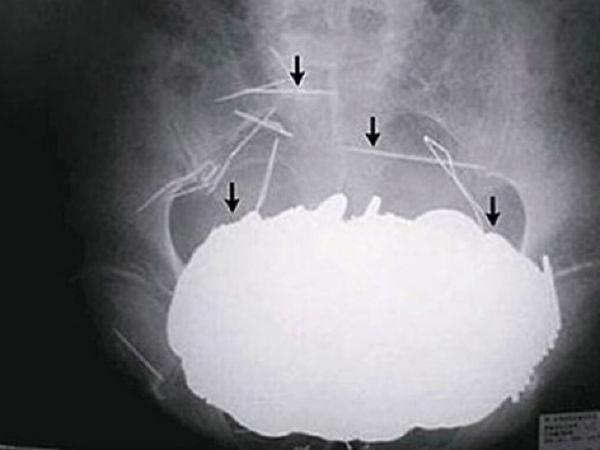

Вы когда-нибудь держали в зубах гвоздь, когда руки заняты молотком? Вот вам снимок мужчины из Китая, который во время работы закашлялся.